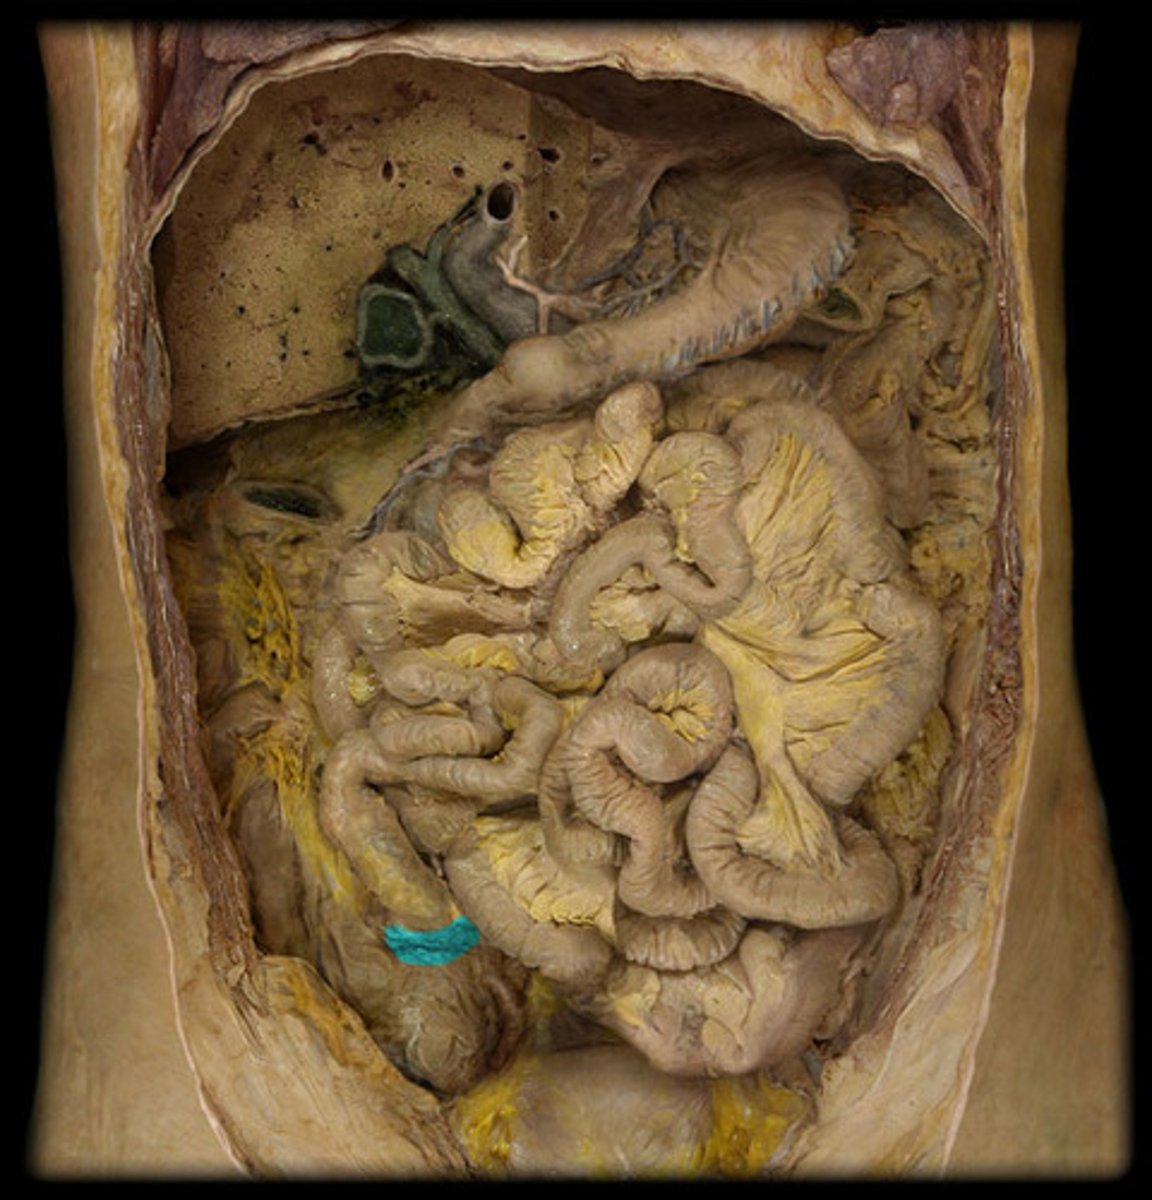

What is this?

Jejunum

Ileum

Ileocecal junction

Teniae coli

Haustra

Epiploic appendices

Cecum

Vermiform appendix

Attached via mesoappendix

Ascending colon

Transverse colon

Descending colon

Sigmoid colon